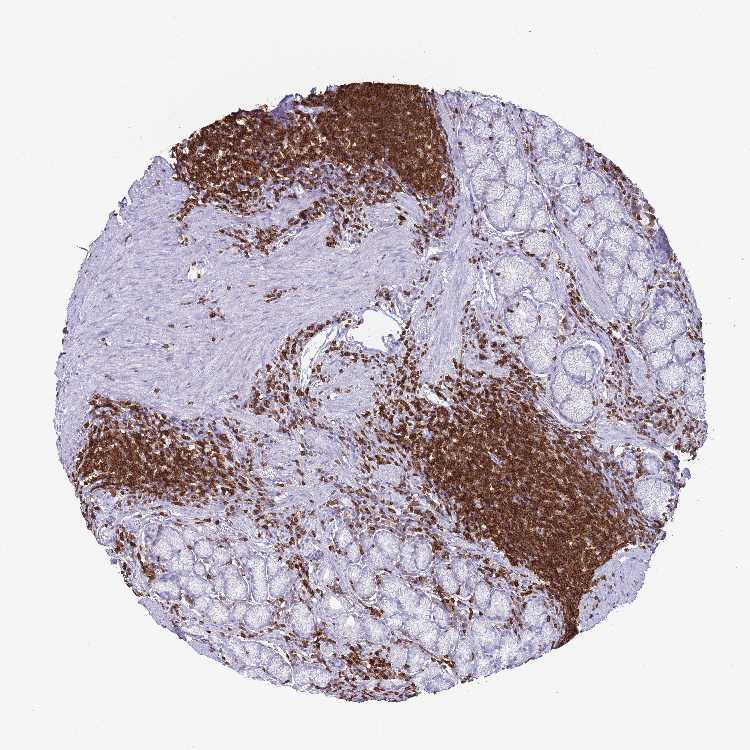

STOMACH 1 - Antibody stainingi

Antibody staining in the annotated cell types in the current human tissue is reported as not detected, low, medium, or high, based on conventional immunohistochemistry profiling in selected tissues. This score is based on the combination of the staining intensity and fraction of stained cells.

Each image is clickable and will lead to virtual microscopy that enables deeper exploration of all samples and also displays staining intensity scores, fraction scores and subcellular localization as well as patient and tissue information for each sample.

Antibody HPA046700Antibody HPA076024

Glandular cells Not detectedMedium